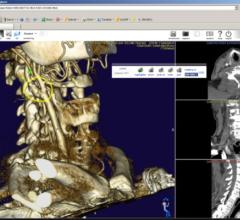

Fovia Medical, Inc. announced the introduction of an expanded high definition volume rendering software suite, featuring F.A.S.T. HDVR, at RSNA 2014.

Claron Technology debuted Nil 4.0 and its Picture Archive and Communication System (PACS) 3.0 diagnostic viewer at the 2014 Radiological Society of North America (RSNA) annual meeting.